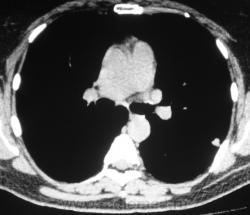

Произведена КТ.

КТ хотелось бы посмотреть в dicom-формате, меняя режимы, но на мой взгляд образование содержит известковые включения. Хотя, я не настаиваю, дождемся мнения коллег.

Нет "волшебных методов", можна поставить диф. ряд. Я бы дала такое заключение: хондрогамартрома, дифференцировать с туберкуломой, периферический рак менее вероятен. Можно жизнь прожить с гамартромой, а может озлиться в саркому. На практике был случай, когда лет 10 наблюдалась классическая скиалогически туберкулома, которая за полгода выросла и оказалась аденокарциномой. Таким образом, при любом раскладе, хирургическое лечение не является ошибкой, но решение об операции на легком должен принимать консилиум.

Дело не в желании, а в смысле. Что тут ещё можно сказать? На мой взгляд-мелкая, частично кальцинированная туберкулома.

Да, более туберкулёма.